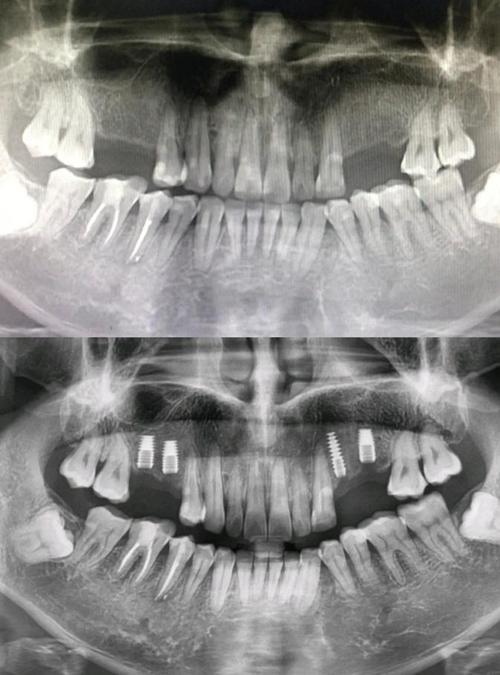

植牙的本质是将人工种植体(类似人工牙根)植入牙槽骨内,最终支撑起牙冠恢复咀嚼功能,这一过程要求种植体必须精准放置在骨量充足、避开重要解剖结构的位置,否则可能导致种植失败、神经损伤、感染等严重后果,而CT检查通过三维成像,能够为医生提供以下关键信息:

牙槽骨的骨高度、宽度、密度是决定能否植牙及选择何种种植体的核心指标,传统X光片(如根尖片、曲面断层片)是二维影像,存在放大失真、重叠干扰等问题,无法准确测量骨量,下颌骨后区的牙槽骨可能因吸收呈现“倒凹”形态,二维片容易误判骨量充足,实际三维CT才能清晰显示骨缺损区域,避免种植体穿出骨壁。

口腔内分布着密集的神经、血管,如下颌的“下牙槽神经管”(内有神经血管束,损伤会导致下唇麻木)、上颌的“上颌窦”(底部与后牙区牙槽骨相邻,穿刺可能引发感染),CT能精准定位这些结构的走行、位置及与牙槽骨的距离,当后牙区骨高度不足5mm时,CT可明确上颌窦底的位置,判断是否需要“上颌窦内提升”或“外提升”手术,避免盲目操作导致上颌窦穿孔。

制定个性化手术方案,提升成功率

通过CT三维重建,医生可在术前模拟种植体植入的路径、角度、深度,选择最适合的种植体型号(如短种植体、窄直径种植体),对于骨量严重不足的患者,CT能明确植骨的范围和量(如自体骨、骨粉填充量),避免术中临时调整方案,数据显示,术前CT引导的植牙手术,成功率比单纯依靠经验提升15%-20%,尤其适用于全口种植、即刻种植等复杂病例。

CT不仅能评估术前骨条件,还能在术后通过对比种植体周围骨的密度变化,判断骨结合情况(即种植体与骨组织融合程度),若发现骨吸收异常,可及时干预,避免种植体松动脱落。